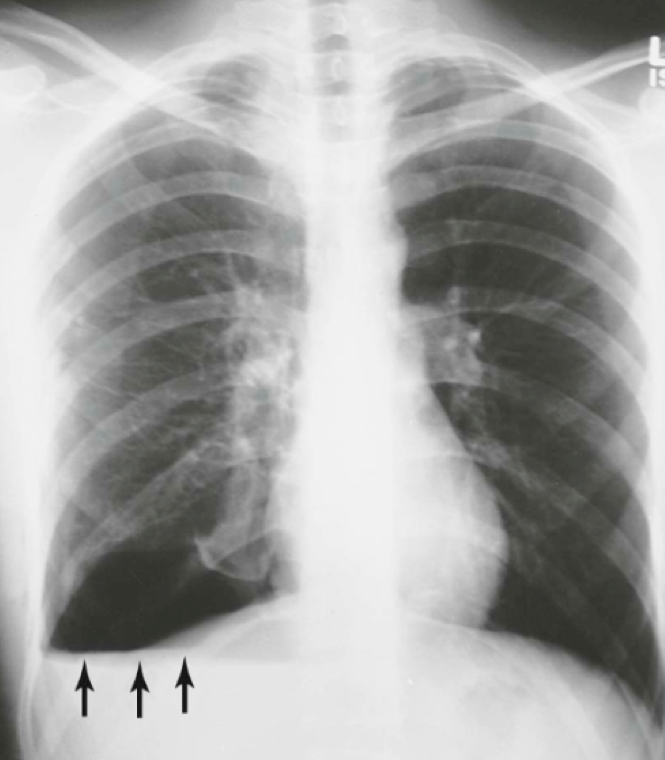

Question 24

Question

What does this CXR tell you?

Answer

• Hydropneumothorax

• Tension Pneumothorax

• Pneumomediastinum

• Pneumothorax